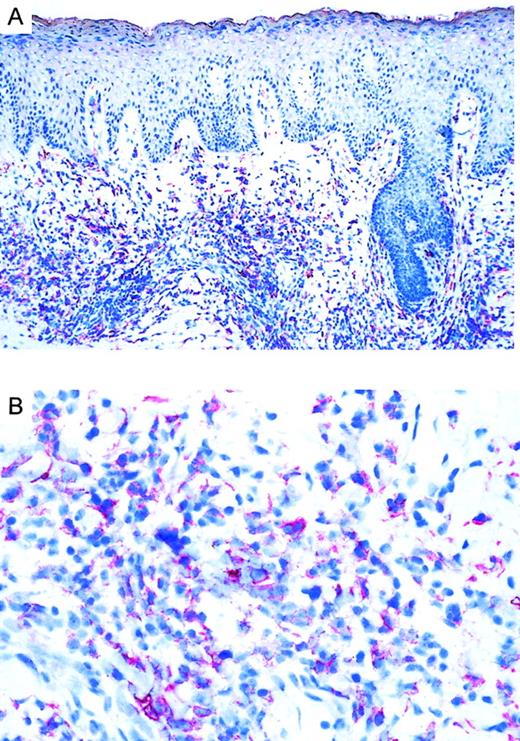

CCR3 ligand eotaxin/CCL11 is expressed by CD30+CTCL

Immunoreactivity of eotaxin in CTCL.

(A) Eotaxin/CCL11 immunoreactivity in cryosection of CD30−CTCL with the use of the alkaline phosphatase/anti–alkaline phosphatase method. Eotaxin/CCL11 is present only in connective tissue cells; tumor cell staining is negative. Original magnification, × 400. (B) Eotaxin/CCL11 immunoreactivity in cryostat section of CD30+ large-cell CTCL with the use of the alkaline phosphatase/anti–alkaline phosphatase method. Eotaxin/CCL11 is present in connective tissue cells and tumor cells, which were CD30+ in serial sections (data not shown). Original magnification, × 400.

The CCR3 ligand eotaxin/CCL11 is known to be produced by human dermal fibroblasts.44,45 Eotaxin/CCL11 not only has agonistic functions but is also a natural antagonist for CCR2.46 Our data demonstrate the presence of eotaxin/CCL11 protein in skin of CTCL lesions (Table 1; Figure 4). In CD30+ as well as in CD30− CTCL, we found expression of eotaxin/CCL11, which was associated with connective tissue cells, most likely fibroblasts, located around the tumor. Only in CD30+ CTCL was eotaxin/CCL11 expression also observed in aggregates of tumor cells. Eotaxin/CCL11 expression at the single-cell level was shown by intracellular eotaxin/CCL11 staining of fresh tumor cell suspensions (Figure 5). Eotaxin/CCL11 expression by lymphoma cells may lead to homotypic aggregation, observed as cohesive clusters of tumor cells, a characteristic of CD30+ anaplastic lymphomas,28 and an amplification of tumor cell homing to the skin. Down-regulation of the receptor in the presence of high eotaxin/CCL11 concentrations may keep lymphoma cells in skin. In this regard, it is of interest that epidermotropic CD30− CTCLs were shown to be associated with epidermal expression of IFN-γ–inducible protein-10 (IP-10) and monokine induced by IFN-γ (Mig).47 Thus, different sets of chemokines produced by different cellular constituents might have an impact on the nature of the malignant infiltrate.